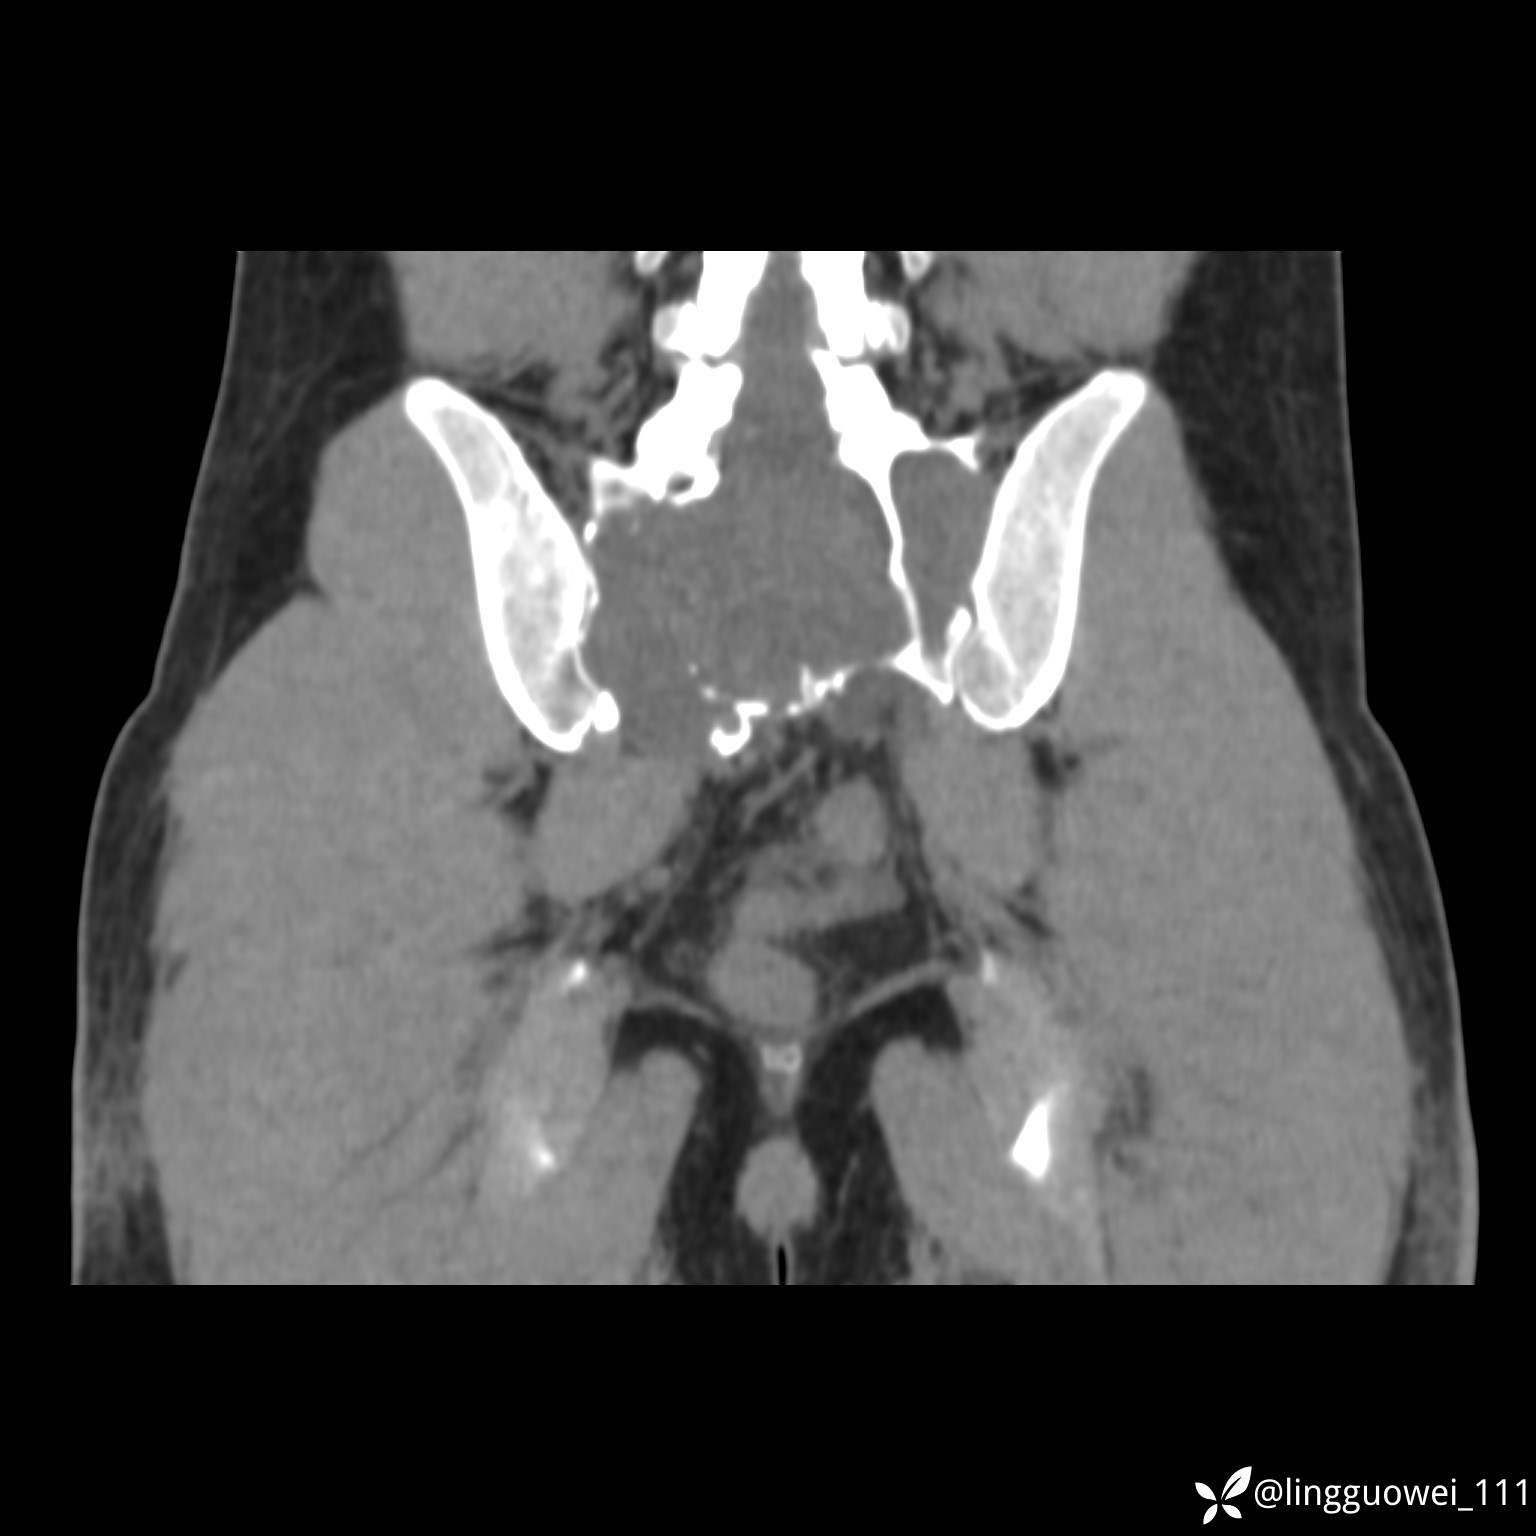

动脉期:

img